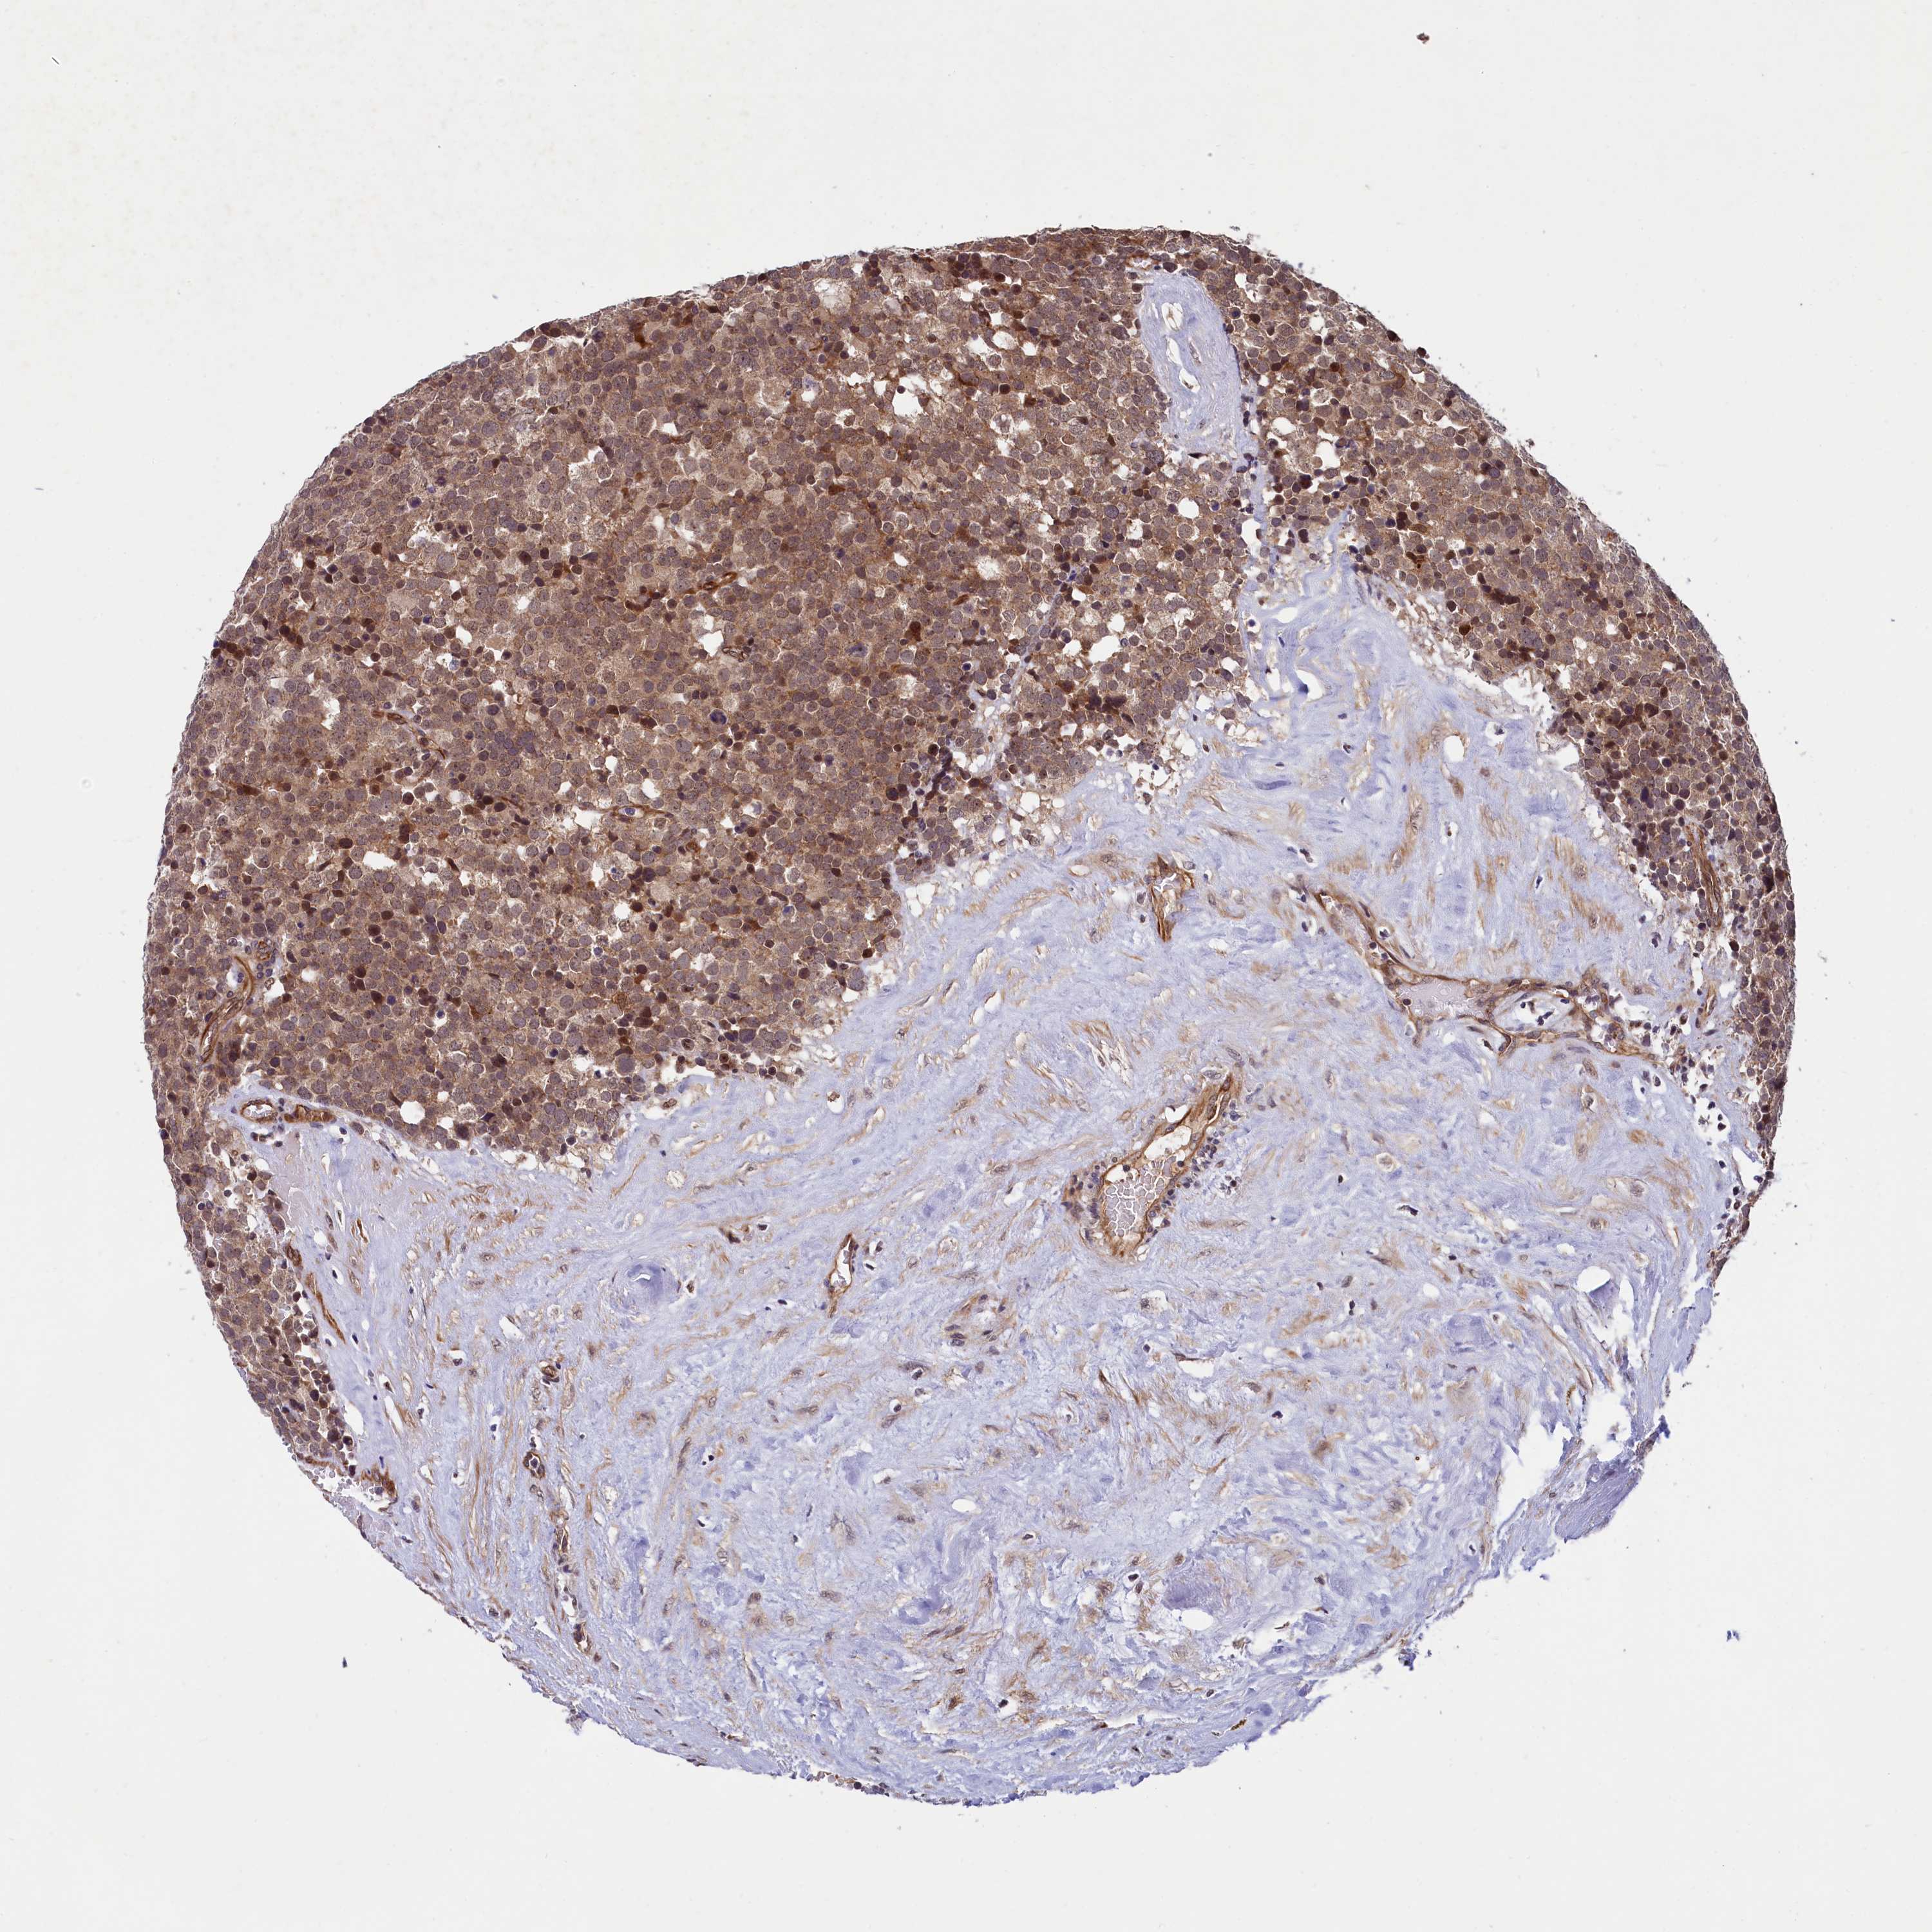

TESTIS CANCER - Protein expressioni

A mouse-over function shows sample information and annotation data. Click on an image to view it in a full screen mode. Samples can be filtered based on level of antibody staining by selecting one or several of the following categories: high, medium, low and not detected. The assay and annotation is described here.

Note that samples used for immunohistochemistry by the Human Protein Atlas do not correspond to samples in the TCGA dataset.

Antibody stainingi

Antibody staining in the annotated cell types in the current human tissue is reported as not detected, low, medium, or high, based on conventional immunohistochemistry profiling in selected tissues. This score is based on the combination of the staining intensity and fraction of stained cells.

Each image is clickable and will lead to virtual microscopy that enables deeper exploration of all samples and also displays staining intensity scores, fraction scores and subcellular localization as well as patient and tissue information for each sample.

Antibody HPA039634

Antibody HPA048127

Staining

High

Medium

Low

Not detected

Intensity

Strong

Moderate

Weak

Negative

Quantity

>75%

75%-25%

<25%

None

Location

Nuclear

Cytoplasmic/membranous

Cytoplasmic/membranous,nuclear

Carcinoma, Embryonal, NOS

Seminoma, NOS

Urothelial carcinoma, High grade